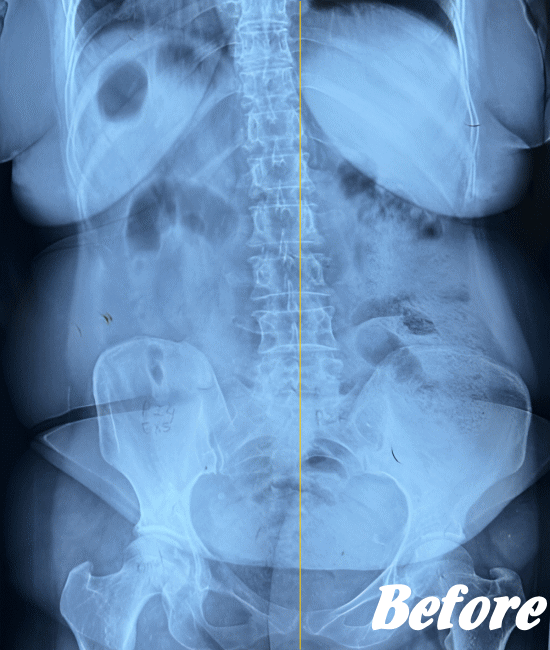

レントゲン、CT、MRIといった画像診断などで坐骨神経痛の原因となる病気(例えば、ヘルニアや脊柱管狭窄症など)が見つかれば、その治療を行います。原因となる病気が見つからない場合は、第一選択肢として、保存療法が適応されます。

HALOカイロプラクティック☆平和島整体院では、仙腸関節や腰、股関節などの部位を解剖学的に正しい状態へ戻すことで、筋肉をゆるめ、関節の詰まりを広げ、圧迫されてしまった神経を解放し、痛みや痺れのない状態へと回復させます。

また、首(頚椎)の歪みにより腰に負担がかかることで坐骨神経痛を発症することもあるため、首も調整します。

ただし、歩行に支障をきたすような激しい痛みの場合は、「股関節のズレが酷い」「腰椎の椎間が詰まっている」「ヘルニアが突出している」「仙腸関節が炎症を起こしている」…等々、通常よりも症状が悪化しているため施術回数が長引くことをご理解いただいたうえで、当院へお越し下さい。